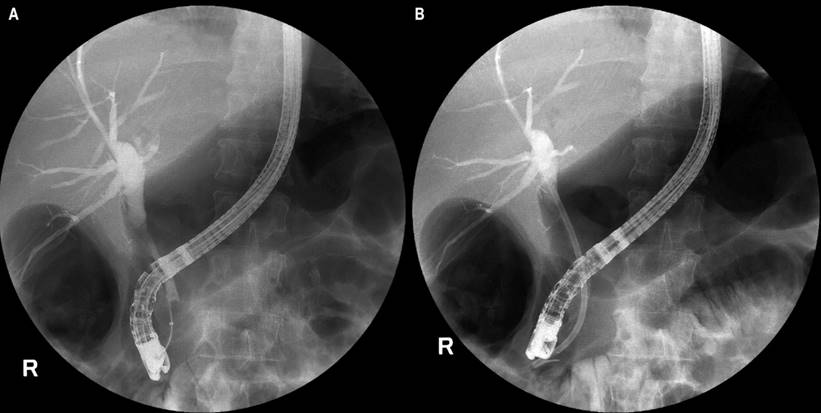

En la CPRE se evidenció una estrechez de la vía biliar común, en la unión del tercio proximal con el tercio medio, con dilatación proximal a la confluencia de los conductos hepáticos (Figura 3A). Se realizó una papilotomía con drenaje de líquido biliar purulento y extracción de los cálculos con canastilla y balón. Se decidió la inserción de un stent de teflón de 10 Fr de 10 cm con un adecuado drenaje (Figura 3B).

Figura 3 CPRE. A. Dilatación de la vía biliar en la unión del tercio proximal con el tercio medio de la vía biliar común, dilatación proximal a la confluencia de los conductos hepáticos. B. Después de la inserción de stent de 10 Fr de 10 cm de teflón. Archivo de Imágenes del Hospital Universitario Hernando Moncaleano Perdomo de Neiva.